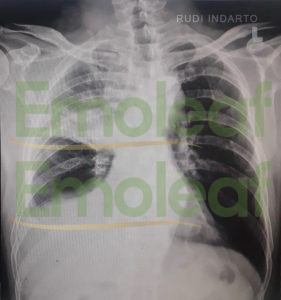

Esok harinya saya segera periksa. Hasil rontgen menunjukan ada cairan yang masuk ke paru dan Saya divonis kanker paru std 3. Dianjurkan kemo, tapi saya belum cukup dana, jadi saya tidak lakukan.

Hasil Rontgen Paru (16 April 2022)

20 September 2022 Saya cek Rontgen kembali. Hasil rontgen menunjukan bahwa Paru – Paru sudah bersih dari kanker dan tidak ada cairan sehingga tidak diperlukan operasi.

20 September 2022, Hasil Rontgen Paru – Paru bersih